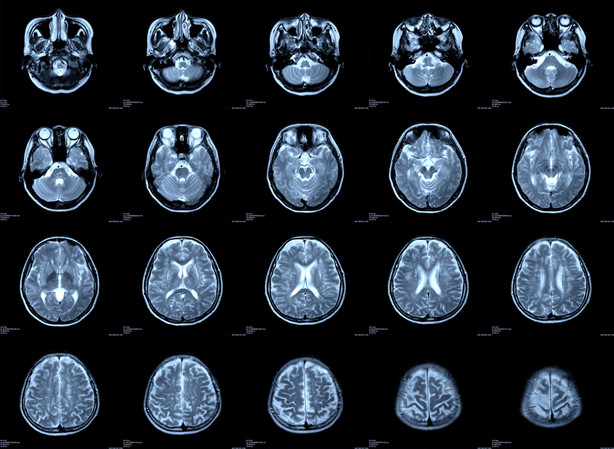

Getting an MRI at TaylorMed is a flat fee of $399. Compared to the $2,611 average fee of a hospital MRI in the U.S., it’s a price you can’t beat. You also won't sacrifice quality at TaylorMed—Dr. Taylor only uses the best equipment. Their MRI machine has a 1.5T magnet and is the gold standard of image quality.